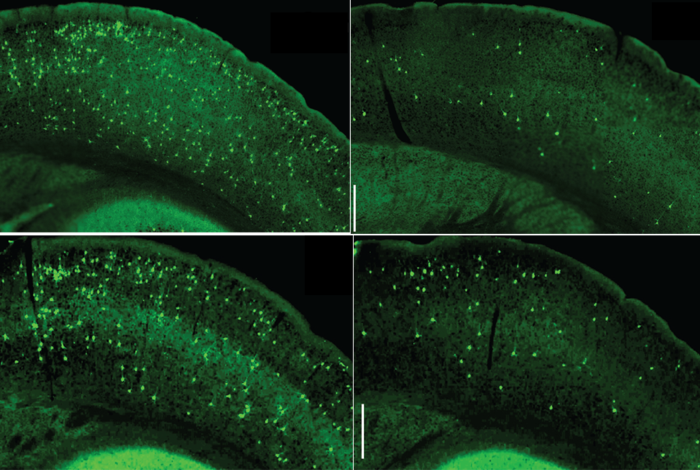

In another tau mouse model, with tau tangle formed in aged neurons, the researchers showed that the inactivation of microglial NF-κB shifted the microglia almost entirely out of their inflammatory, disease-associated state, restoring a much more normal cell appearance and pattern of gene activity. This shift, which suppresses microglia from disgorging toxic tau seeds, strikingly, prevented key cognitive/memory deficits the mice normally develop in this model.